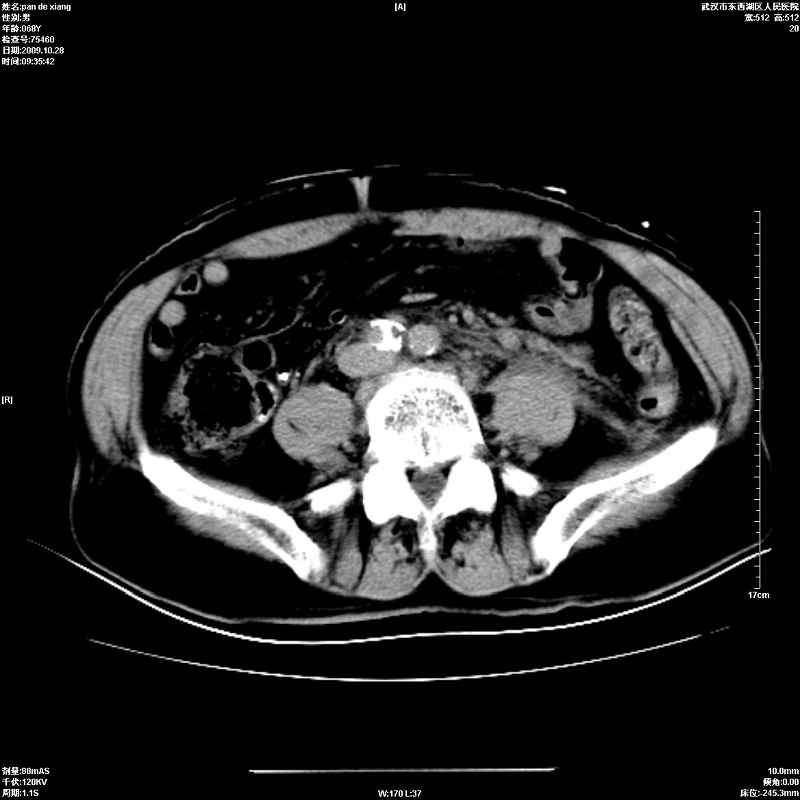

以下是引用杀毒软件在2009-10-28 20:41:00的发言:[br]结合临床考虑---白血病双肾改变或淋巴瘤。

以下是引用zxl51642在2009-10-29 9:59:00的发言:[br]结合临床“单克隆免疫球蛋白血症”,考虑双肾为继发损害并肾功能不全(尿中大量igg及少量iga、igm等大分子免疫球蛋白滤出所致继发损害),椎前软组织肿块为髓外造血。与浆细胞瘤有区别,平扫时有战友说的很清楚。